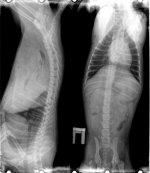

Этот человек в середине октября приобрел у меня здорового щенка. Зовут его Пальтов Олег Николаевич г. Тверь. Через два месяца позвонил мне и заявил, что я продала ему калеку и выслал соответствующие фотографии (давил на то, что у собаки родовая травма или полученная на первых неделях жизни)!!! У щенка обнаружилась травма позвоночника (выслал мне липовое заключение врача и не читаемые снимки - я с ними посетила опытного хирурга, который пришел в ужас и от снимков, и от заключения) и недоразвитие костей таза..заявил, что последние отклонения генетические, но подтвердить документально этого не смог. Требовал, чтобы я забрала или обменяла ему щенка. Врач в клинике ему сказал, что шансов на возврат у него нет. Когда я предложила ему забрать щенка обследовать и заняться его лечением он сначала согласился, так как сказал что собакой заниматься он не желает. Собрались уже ехать к нему в Тверь, он написал сообщение, что уже продал щенка за копейки в расход! Предлагала вернуть деньги, но он отказался возвращать собаку назад, заявив, что назад пути нет.

На первом фото щенок до отправки, на следующих у горе владельца.

Этот человек в середине октября приобрел у меня здорового щенка. Зовут его Пальтов Олег Николаевич г. Тверь. Через два месяца позвонил мне и заявил, что я продала ему калеку и выслал соответствующие фотографии (давил на то, что у собаки родовая травма или полученная на первых неделях жизни)!!! У щенка обнаружилась травма позвоночника (выслал мне липовое заключение врача и не читаемые снимки - я с ними посетила опытного хирурга, который пришел в ужас и от снимков, и от заключения) и недоразвитие костей таза..заявил, что последние отклонения генетические, но подтвердить документально этого не смог. Требовал, чтобы я забрала или обменяла ему щенка. Врач в клинике ему сказал, что шансов на возврат у него нет. Когда я предложила ему забрать щенка обследовать и заняться его лечением он сначала согласился, так как сказал что собакой заниматься он не желает. Собрались уже ехать к нему в Тверь, он написал сообщение, что уже продал щенка за копейки в расход! Предлагала вернуть деньги, но он отказался возвращать собаку назад, заявив, что назад пути нет.

На первом фото щенок до отправки, на следующих у горе владельца.